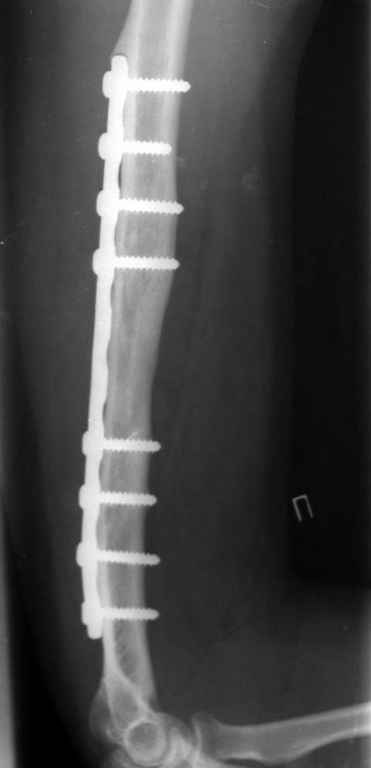

Здравствуйте Владимир! На всех рентгенограммах определяется лизис костной ткани вокруг шурупов, на боковой проекции похоже секвестр, это -- в пользу остеомиелита. Рекомендую: удаление металлоконструкций краевую резекцию концов плечевой кости, ревизию каналов после удаленных шурупов, при наличии признаков остеомиелитических грануляций провести кюретаж. Наложить спице-стержневой АВФ + открытую репозицию отломков. При необходимости проточно- промывное дренирование. Желательно применение Коллапана интраоперационно.